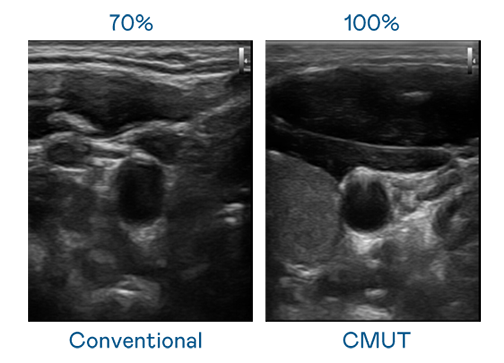

CMUT 技术是一种用电容式微机电元件来产生超音波讯号的技术。与传统 PZT 压电式技术相比,CMUT 频宽增加 30%,更宽频的超音波讯号让影像解析度大幅提升,是实现高影像品质医疗超音波扫描、促进精准医疗发展的关键技术。

大频宽带来超清晰影像

超音波影像的解析度高低,首先取决于探头能发出的讯号频宽。ks凯时 CMUT 可提供高清晰的超音波讯号,提供高频宽、高灵敏度、影像纹理细节更高的超音波影像,协助医护人员缩短影像判读时间及利用精准的医疗影像进行诊断。